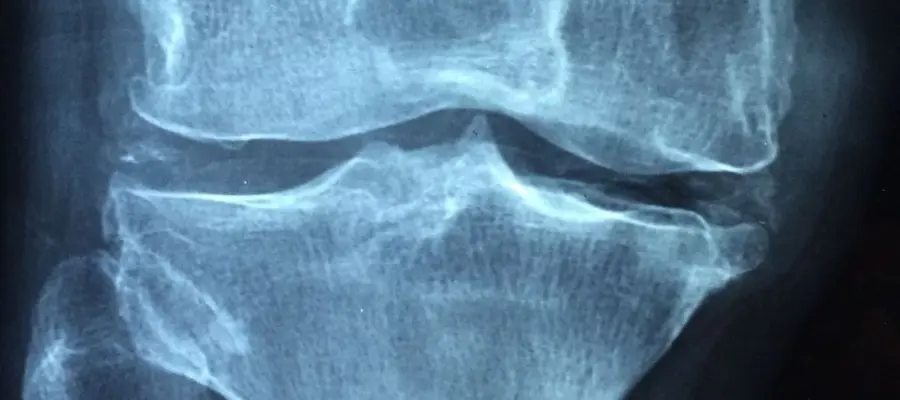

Loãng xương là tình trạng mật độ xương giảm, khiến xương trở nên yếu và dễ gãy hơn. Bệnh thường